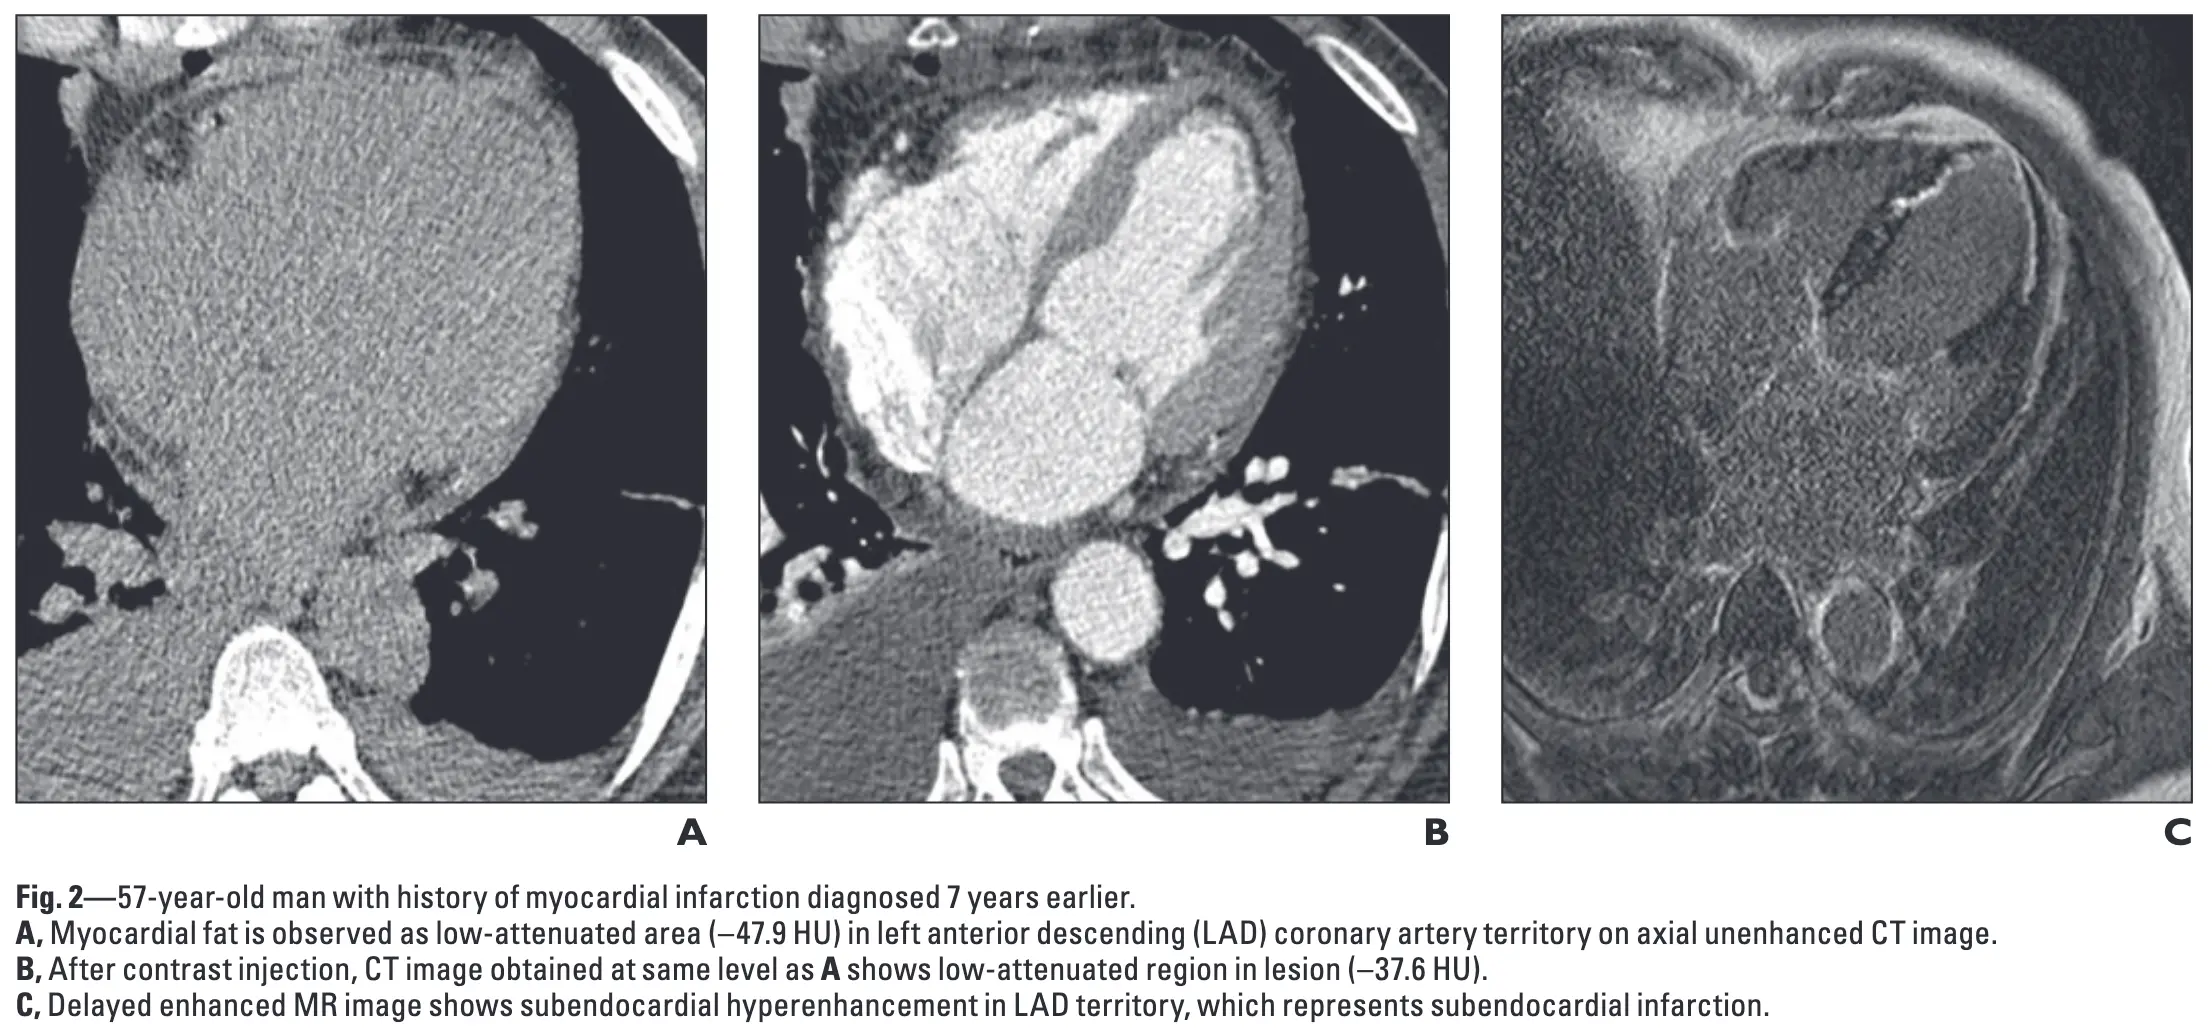

Ischemia may appear as subendocardial hypoattenuation, fatty metaplasia or calcification

- Figure source: 1

Ahn SS, Kim YJ, Hur J, Lee HJ, Kim TH, Choe KO, Choi BW. CT detection of subendocardial fat in myocardial infarction. AJR Am J Roentgenol. 2009 Feb;192(2):532-7. doi: 10.2214/AJR.08.1608. PMID: 19155421. ↩